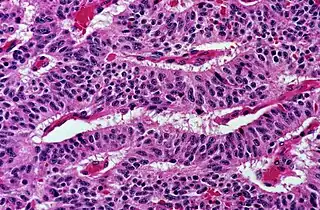

This can be done to slides processed by the chemical fixation or frozen section slides. To see the tissue under a microscope, the sections are stained with one or more pigments. The aim of staining is to reveal cellular components; counterstains are used to provide contrast.

The most commonly used stain in histology is a combination of hematoxylin and eosin (often abbreviated H&E). Hematoxylin is used to stain nuclei blue, while eosin stains the cytoplasm and the extracellular connective tissue matrix of most cells pink. There are hundreds of various other techniques which have been used to selectively stain cells. Other compounds used to color tissue sections include safranin, Oil Red O, congo red, silver salts and artificial dyes. Histochemistry refers to the science of using chemical reactions between laboratory chemicals and components within tissue. A commonly performed histochemical technique is the Perls' Prussian blue reaction, used to demonstrate iron deposits in diseases like Hemochromatosis.[2]

Recently, antibodies have been used to stain particular proteins, lipids and carbohydrates. Called immunohistochemistry, this technique has greatly increased the ability to specifically identify categories of cells under a microscope. Other advanced techniques include in situ hybridization to identify specific DNA or RNA molecules. These antibody staining methods often require the use of frozen section histology. These procedures above are also carried out in the laboratory under scrutiny and precision by a trained specialist medical laboratory scientist (a histoscientist). Digital cameras are increasingly used to capture histopathological images.